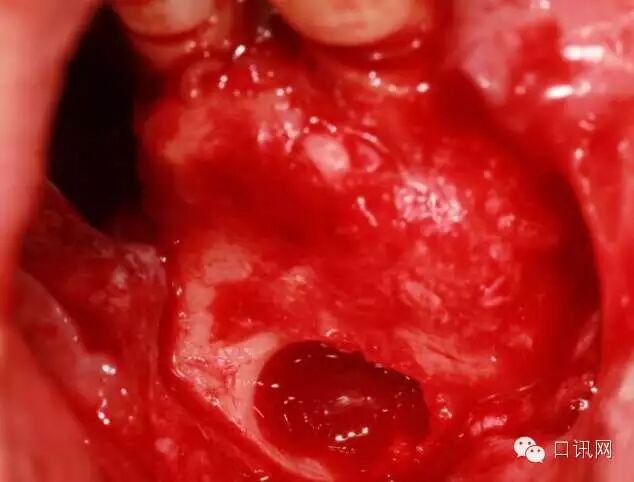

进一步剥离下壁、近远中、腭侧壁窦膜口腔临床执业医师

使用取骨钻在4,5根方取骨口腔医学技术

自体骨与骨粉混合填入窦内口腔修复工艺

植入两颗植体综合治疗椅,牙片机,洁牙机

缝合执业助理医师,待遇优厚,底薪加提成

术后6,7牙位CT片,显示充足的植骨量按照科学发展理念与时俱进,适应时代需要,